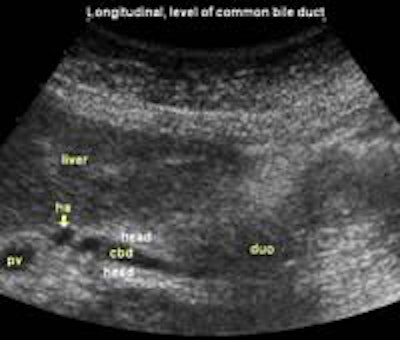

The following study describes anatomical landmarks in the ordinary pancreas of a thin patient:

Transverse planes in caudal direction: